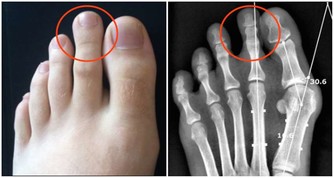

口腔潰瘍的情況下密切接吻有可能感染艾滋病。

艾滋病的傳染要滿足三個條件:傳染源,傳播途徑,易感人群。

即使會傳染,但實際上有很多前提條件:

1.一方確實感染了艾滋病毒;

2.感染者沒有經過任何抗病毒治療;

3.口腔有潰瘍出血。